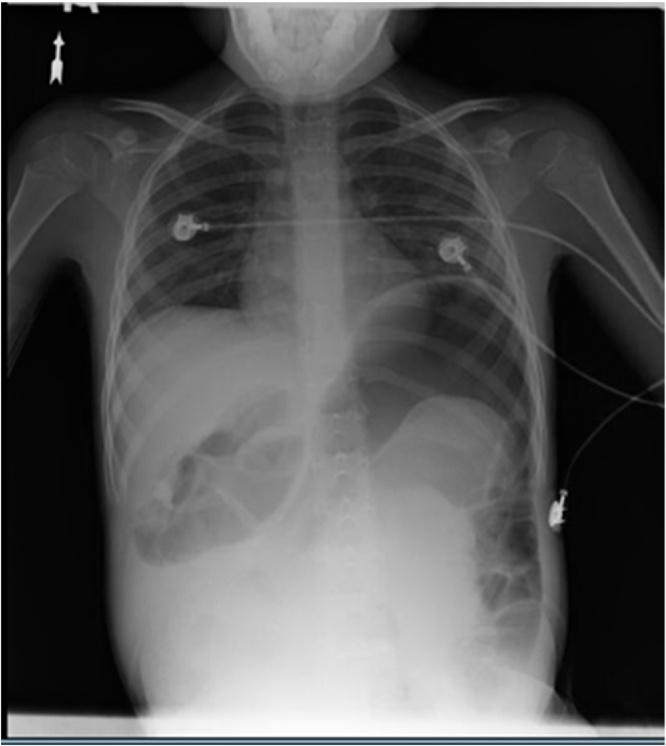

The patient is a 7 year-old girl with a history of trichotillomania with trichophagia as a young child who presented with abdominal pain, nausea, and vomiting, consistent with a gastric outlet obstruction. She had an exploratory laparotomy with gastrostomy performed revealing a 18cm by 18cm trichobezoar with extension into the small bowel.

该患者是一名7岁女孩,幼儿期有拔毛癖伴食毛症病史,现出现腹痛、恶心和呕吐,符合胃出口梗阻的表现。她接受了剖腹探查术并进行了胃造口术,发现一个18厘米×18厘米的毛石,延伸至小肠。